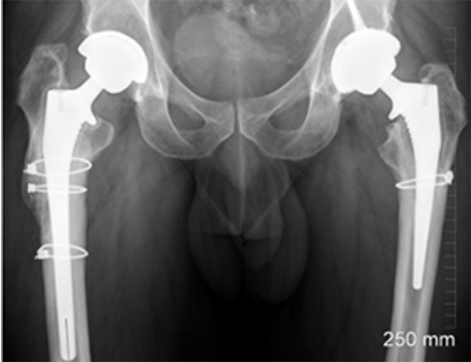

A middle-aged patient came to the clinic with severe pain and limited mobility in his left hip. Previously, he had undergone bilateral hip replacements that included modular necked femoral stems with ceramic-on-ceramic (CoC) bearings. However, the modular design led to corrosion between the titanium femoral stem and the cobalt-chromium neck, causing metal debris and an adverse tissue reaction in his left hip.

The challenge was in addressing the corrosion-related inflammation without exacerbating the damage to the surrounding bone, as the femoral stem was well fixed. Unlike cases with pseudotumors, the patient’s problem originated from metal debris due to the interaction of different alloys in the modular components.

Imaging studies confirmed the presence of metal debris and inflammation around the implant, particularly affecting the left hip. Despite the ceramic-on-ceramic bearing being intact, the corrosion at the modular junction between the neck and the stem was the main culprit. The diagnosis was an adverse reaction to metal debris, secondary to modular neck corrosion.

The surgery was successful, and at his six-week follow-up, the patient reported pain-free mobility and had resumed his daily activities. Imaging showed that the new primary stem had successfully integrated with the bone. At the two-year follow-up, the patient had a well-functioning hip, with no complications and clear evidence of bone growth around the implant, confirming the efficacy of the surgical approach.

This case represents ALTR with CoC. ALTR was characterized by tissue inflammation and extensive fluid accumulation around the ceramic implants. However, ALTR was not caused by the ceramic implant but by corrosion, which occurred between the titanium femoral stem and the cobalt-chromium neck.